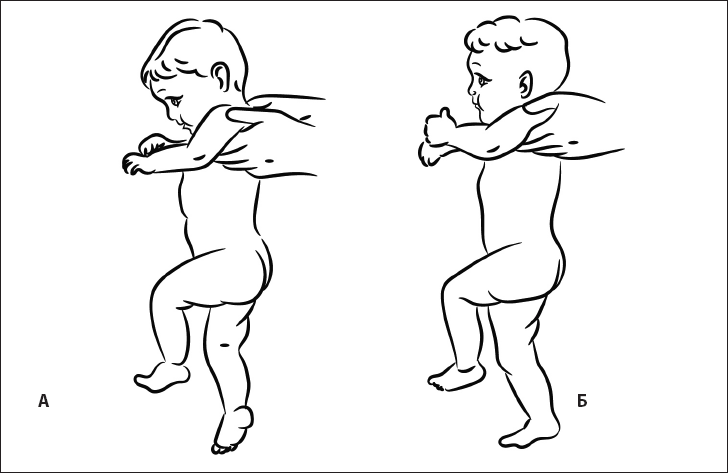

Когда ребенок долго лежит на спине, он пытается перевернуться. Его побуждает к этому рефлекс переворачивания (рис. 17).

Он состоит из координации нескольких движений: разворот ног, поворот туловища, разворот плечевого пояса и поворот головы. В дальнейшем эта последовательность движений реализуется при формировании спиралевидной МФЦ. Она начинается от боковых мышц стопы и заканчивается на руке и шее.

Патобиомеханика. Если по какой-либо причине выключаются мышцы, составляющие одну из цепей, возникает деформация статики в виде бокового смещения таза, мышечно-тонического сколиоза, наклона головы в сторону. Поэтому, чтобы убрать одну из найденных деформаций, необходимо восстановить полноценность МФЦ.

Рис. 17. Рефлекс переворачивания.

2. Рефлекс разгибания головы

При переворачивании на живот ребенок вытягивает ноги, разгибает туловище и далее разгибает голову (рис. 18).

Рис. 18. Рефлекс разгибания головы.

Это движение обеспечивается активацией длинных разгибателей шеи. Благодаря ему ребенок, который лежит на животе, не задыхается.